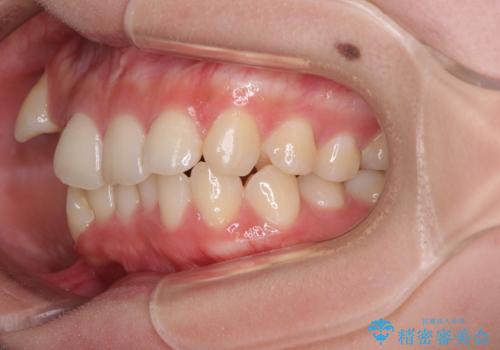

八重歯の抜歯矯正 補助装置とワイヤーを併用したインビザライン矯正治療

骨格的に下顎が左側に変位していたため、上下正中を合わせることは困難であることは分かっていましたが、可能な限り合わせることができました。

骨格的なズレがあると仕上げの段階で奥歯の咬み合わせが不安定となるため、予定よりやや長期間となりました。